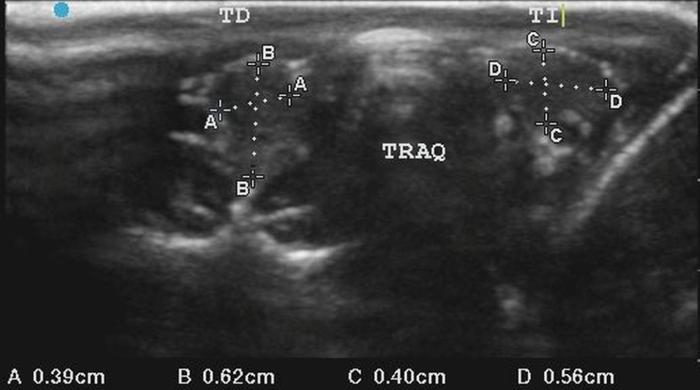

La glándula tiroides en perros y gatos está constituida por dos lóbulos situados a ambos lados de la tráquea cervical, con disposición longitudinal y una forma fusiforme o alargada que se extiende desde el cartílago cricoides hasta la entrada torácica superior2. En condiciones normales, cada lóbulo presenta contornos bien definidos, cápsula hiperecogénica delgada y parénquima homogéneo, con una ecogenicidad generalmente igual o ligeramente superior al músculo esternohioideo adyacente3,8. En la imagen transversal, los lóbulos suelen adoptar una configuración oval o ligeramente triangular (Figura 1); en longitudinal, se observa una forma alargada con extremos redondeados y orientación paralela a los vasos carotídeos y la tráquea1 (Figura 2).

En perros, el tamaño de la glándula tiroides muestra una correlación directa con el peso corporal. Algunos estudios han demostrado que las dimensiones tiroideas aumentan progresivamente en razas de mayor talla, manteniéndose proporciones constantes entre largo, ancho y alto de los lóbulos6. En gatos, la glándula tiroides suele ser más pequeña, delgada y elongada, con lóbulos habitualmente simétricos en animales sanos. La vascularización normal puede ser visualizada mediante Doppler color como un flujo periférico tenue y homogéneo, sin evidencia de hipervascularización focal ni penetración central4.

La localización anatómica superficial de la glándula, junto con su estructura relativamente uniforme, facilita su identificación mediante ultrasonografía de alta resolución. Entre los reparos anatómicos más importantes para su localización se encuentran las arterias carótidas comunes (laterales), la tráquea (medial) y los músculos esternotiroideos (ventrales), mientras que el esófago puede constituir una referencia dorsal del lóbulo izquierdo15 (Figuras 3 y 4).

En cuanto a los parámetros ecográficos de referencia, estudios realizados en perros han determinado que los lóbulos tiroideos sanos presentan una longitud entre 13-23 mm, ancho de 3-8 mm y alto de 2-5 mm, con variaciones según raza y tamaño corporal6. En gatos, las dimensiones normales son más pequeñas y oscilan entre 10-17 mm de largo, y 2-4 mm de ancho y alto, dependiendo de la edad y el estado funcional10 (ver además la Tabla 1).

La evaluación bilateral es esencial, ya que la simetría es un hallazgo habitual en glándulas normales, mientras que las asimetrías o presencia de un solo lóbulo visible pueden asociarse a patologías estructurales o funcionales subyacentes.